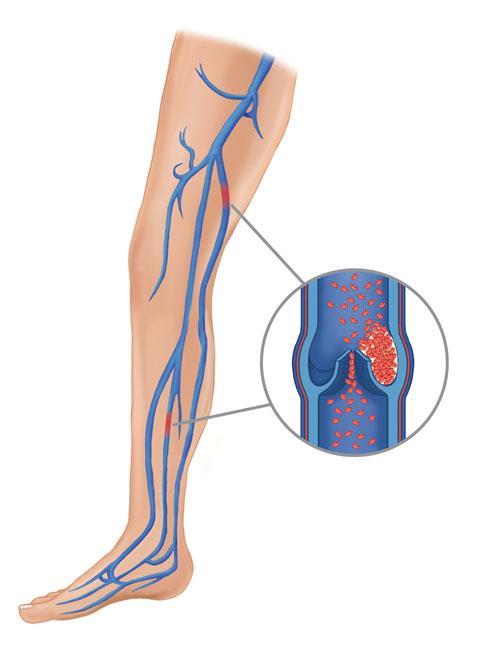

vein thrombosis deep dvt danger clot blood prevention

dvt thrombosis vein

thrombosis vein dvt veins embolism pulmonary drugwatch lungs vessel

thrombosis vein dvt blood